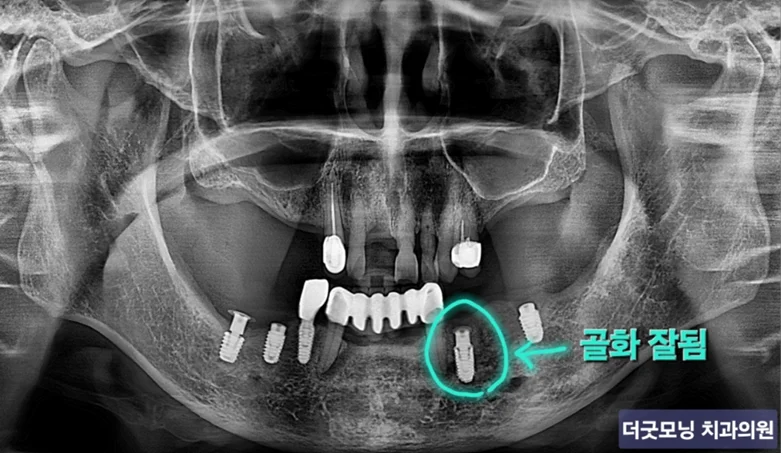

STEP 4 — 3개월 후 경과 확인

3개월 후 파노라마 및 CT 재촬영 결과, 이식된 부위에서 골화가 잘 진행되고 있음을 확인하였습니다.

3개월 후 파노라마 — 골화 진행 확인

3개월 후 CT — 이식 부위 골화 양호